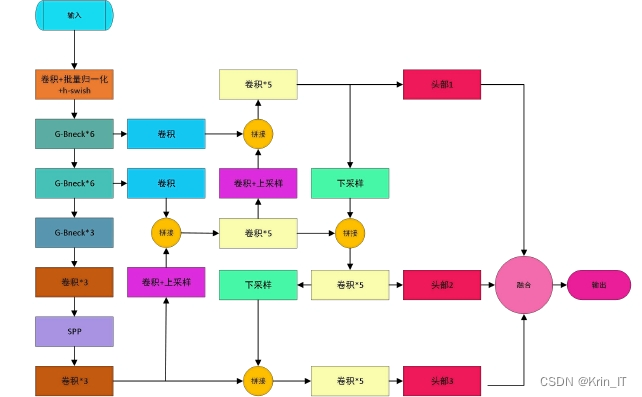

在主干网络的改进方面,原版YOLOv5的主干网络部分大体保留了YOLOv4的结构,但CSPDarknet53由于参数量庞大,对计算机的存储和计算能力要求较高,进而影响了运行速度。为了解决这一问题,研究参考了Ghost bottleneck结构,对其进行了改进。新的Ghost bottleneck结构中引入了前述的时空注意力机制,尽管增加了部分参数,但这一机制是为了适应肺部CT影像中可能出现的多种肺结节而专门设计的,从而能够更准确地提取特征信息。尽管整体计算量有所增加,但相较于YOLOv5原有的CSPDarknet53结构,其计算复杂度仍然显著降低。改进后的Ghost bottleneck结构(简称G-BNeck)通过增强特征提取能力,进一步提升了模型在复杂任务中的表现。

SPP结构是一种特殊的池化层,通过先经过卷积层,再应用不同大小的卷积核进行多尺度特征提取,最后将池化后的信息拼接成全连接层可接受的尺寸,实现动态调整,不需预设图片尺寸。颈部网络则结合了SPP结构与FPN(特征金字塔网络)和PAN(路径聚合网络),采用上采样进行特征融合,并通过直接拼接方式融合不同路径的特征图,从而实现对主干特征网络的参数融合。头部网络保持原YOLOv5结构,仍然作为一阶段检测网络,采用二元交叉熵损失函数计算置信度损失,分别针对有目标物和没有目标物的情况进行定义,以确保模型的准确性和鲁棒性。

以YOLOv5的主体结构为基础,首先将骨干网络部分更改为改进的Ghost bottleneck(G-Bneck)结构,这一改动使得网络更加轻量化,提升了运行效率。随后,在G-Bneck中引入了时空注意力机制,以减少冗余信息对识别效果的影响,增强了模型对关键特征的关注能力。结合SPP结构与FPN(特征金字塔网络)和PAN(路径聚合网络),构建了一个特征深度融合提取网络,实现对目标特征的详尽提取。最终,通过这一改进的网络结构输出预测结果,完成了算法的构建任务。